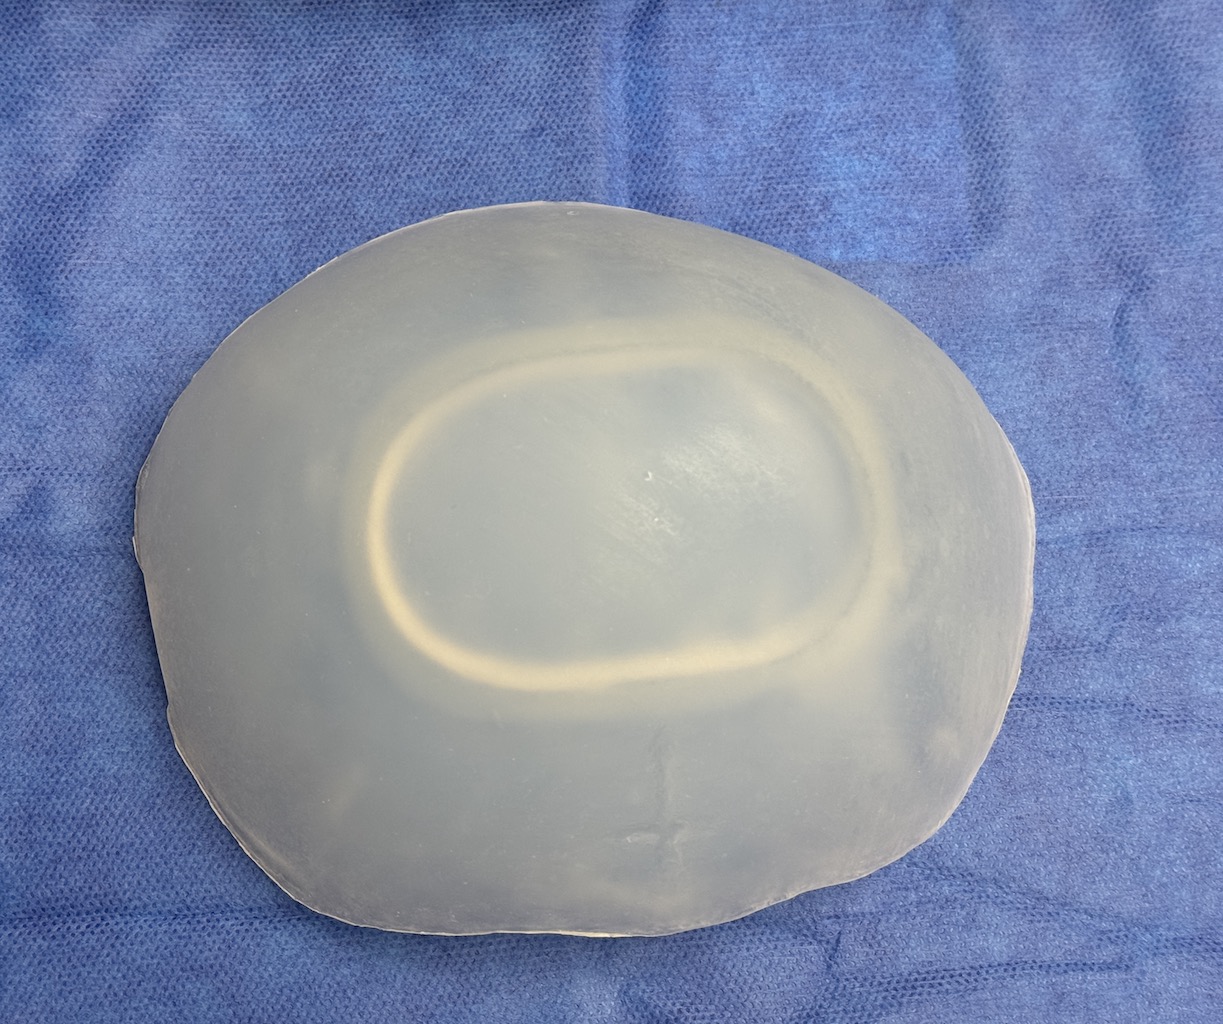

Severe narrowing skull deformity from prior sagittal craniosynostosis repair as an adult.

Complete replacement of entire skull by a custom implant with temporal fat injections.

Severe narrowing skull deformity from prior sagittal craniosynostosis repair as an adult.

Complete replacement of entire skull by a custom implant with temporal fat injections.